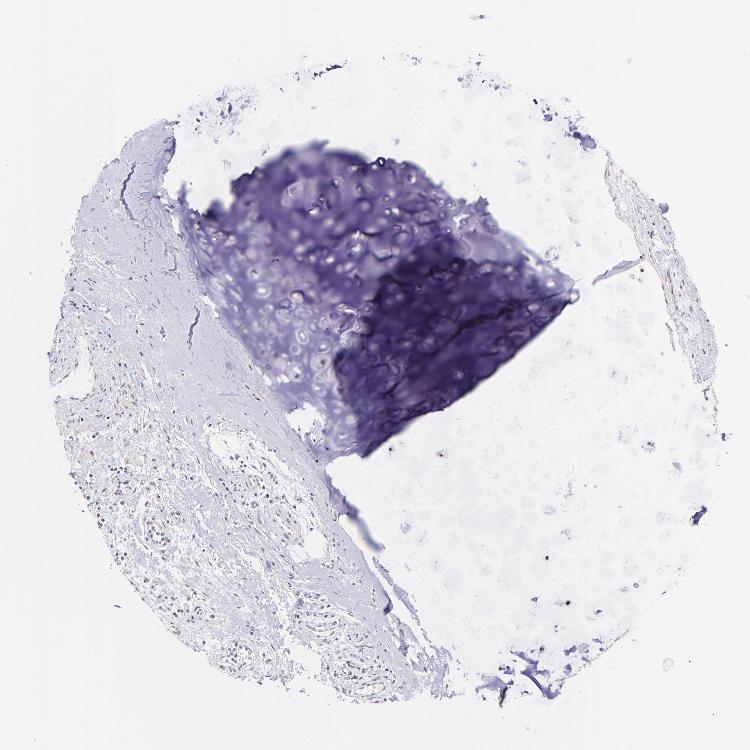

SOFT TISSUE 2 - Antibody stainingi

Antibody staining in the annotated cell types in the current human tissue is reported as not detected, low, medium, or high, based on conventional immunohistochemistry profiling in selected tissues. This score is based on the combination of the staining intensity and fraction of stained cells.

Each image is clickable and will lead to virtual microscopy that enables deeper exploration of all samples and also displays staining intensity scores, fraction scores and subcellular localization as well as patient and tissue information for each sample.

Antibody HPA001923Antibody HPA003908

Fibroblasts MediumNot detected

Peripheral nerve -Not detected